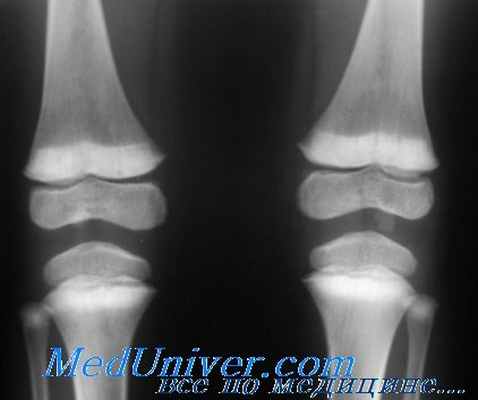

Рентгенограмма нижних конечностей ребенка при рахите из-за синдрома Фанкони

Развиваются различные функциональные дефекты транспорта в проксимальных канальцах, включая нарушенную реабсорбцию глюкозы, фосфатов, аминокислот, бикарбоната, мочевой кислоты, воды, калия и натрия. Наблюдается генерализованная аминоацидурия и, в отличие от цистинурии, повышенная экскреция цистина – наименьшее ее проявление. Основной патофизиологический механизм неизвестен, но вероятно связан с митохондриальными нарушениями. Низкие уровни фосфатов в крови вызывают рахит, который усугубляется сниженной конверсией витамина D в его активную форму в проксимальных канальцах.

При наследственном синдроме Фанкони основные клинические проявления – проксимальный тубулярный ацидоз, гипофосфатемический рахит, гипокалиемия, полиурия и полидипсия – обычно развиваются в детстве.

При наследственном синдроме Фанкони проксимальный тубулярный ацидоз, гипофосфатемический рахит, гипокалиемия, полиурия и полидипсия обычно развиваются в раннем детстве.